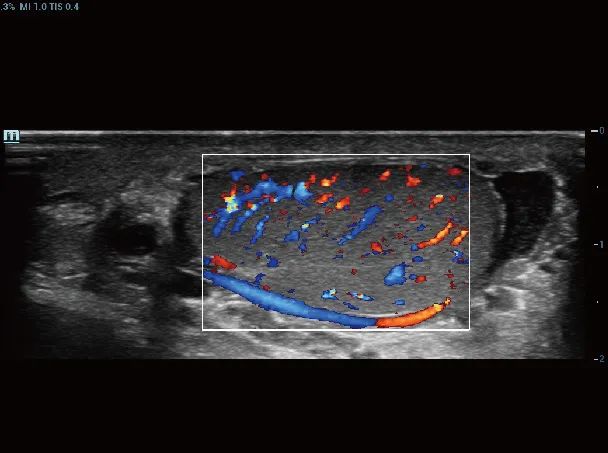

睾丸血流

动态向量血流V-Flow

通过彩色编码的向量箭头来追踪血流速度的大小和方向,生动且准确地显示外周血管的血流动力学特征,包括血管的管径、走行、分布和血管的丰富程度。依靠其高性能的彩色多普勒超声功能,能够显示直径在两毫米以下的细小血管,以及低速血流、低流量的血流,用于评价脏器血流灌注和病灶的血供特点,且无角度依赖,是极具价值的血流动力学研究工具。